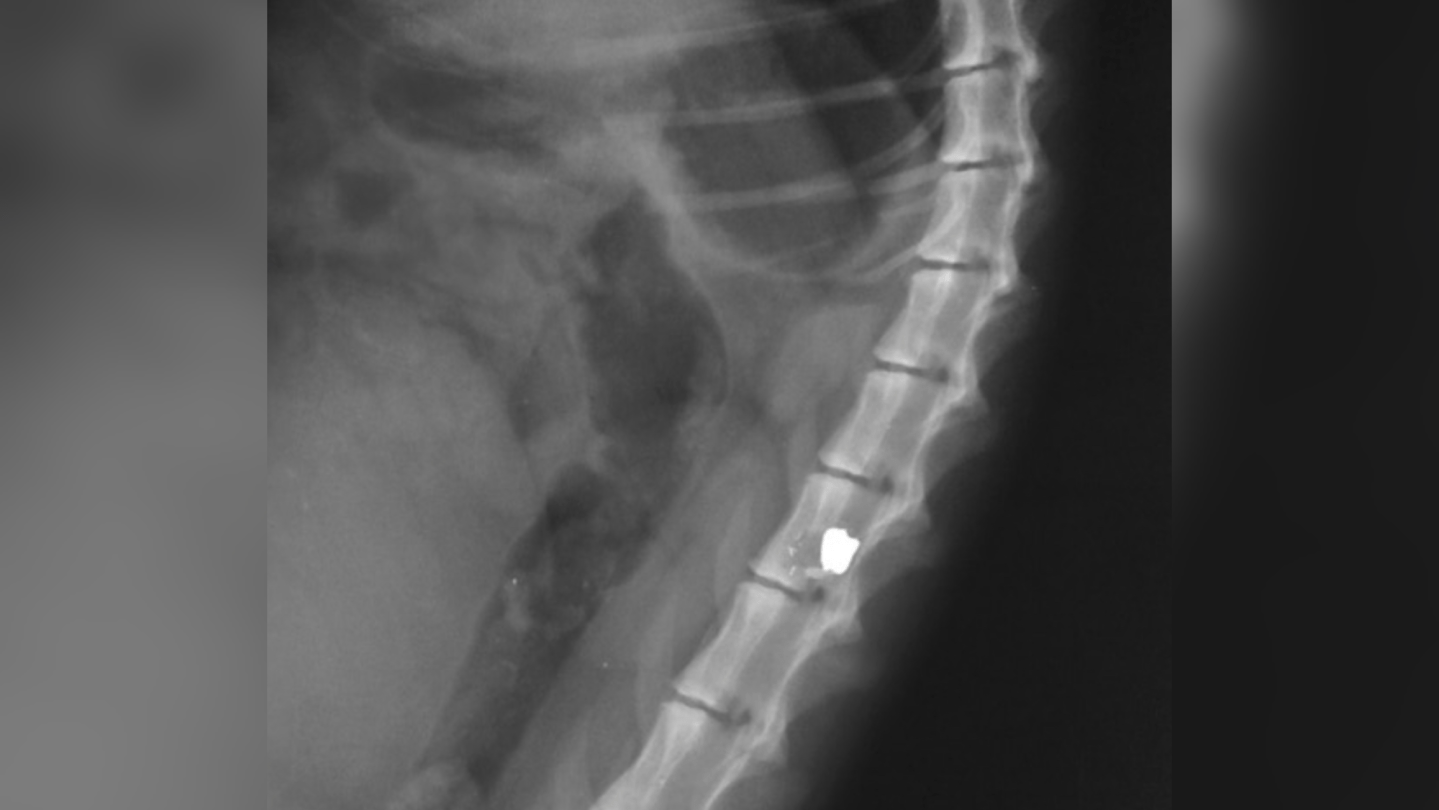

According to the family member who is close to the matter and the shooting victim, one of the bullets fired by the police caught the man in the area of his spine.